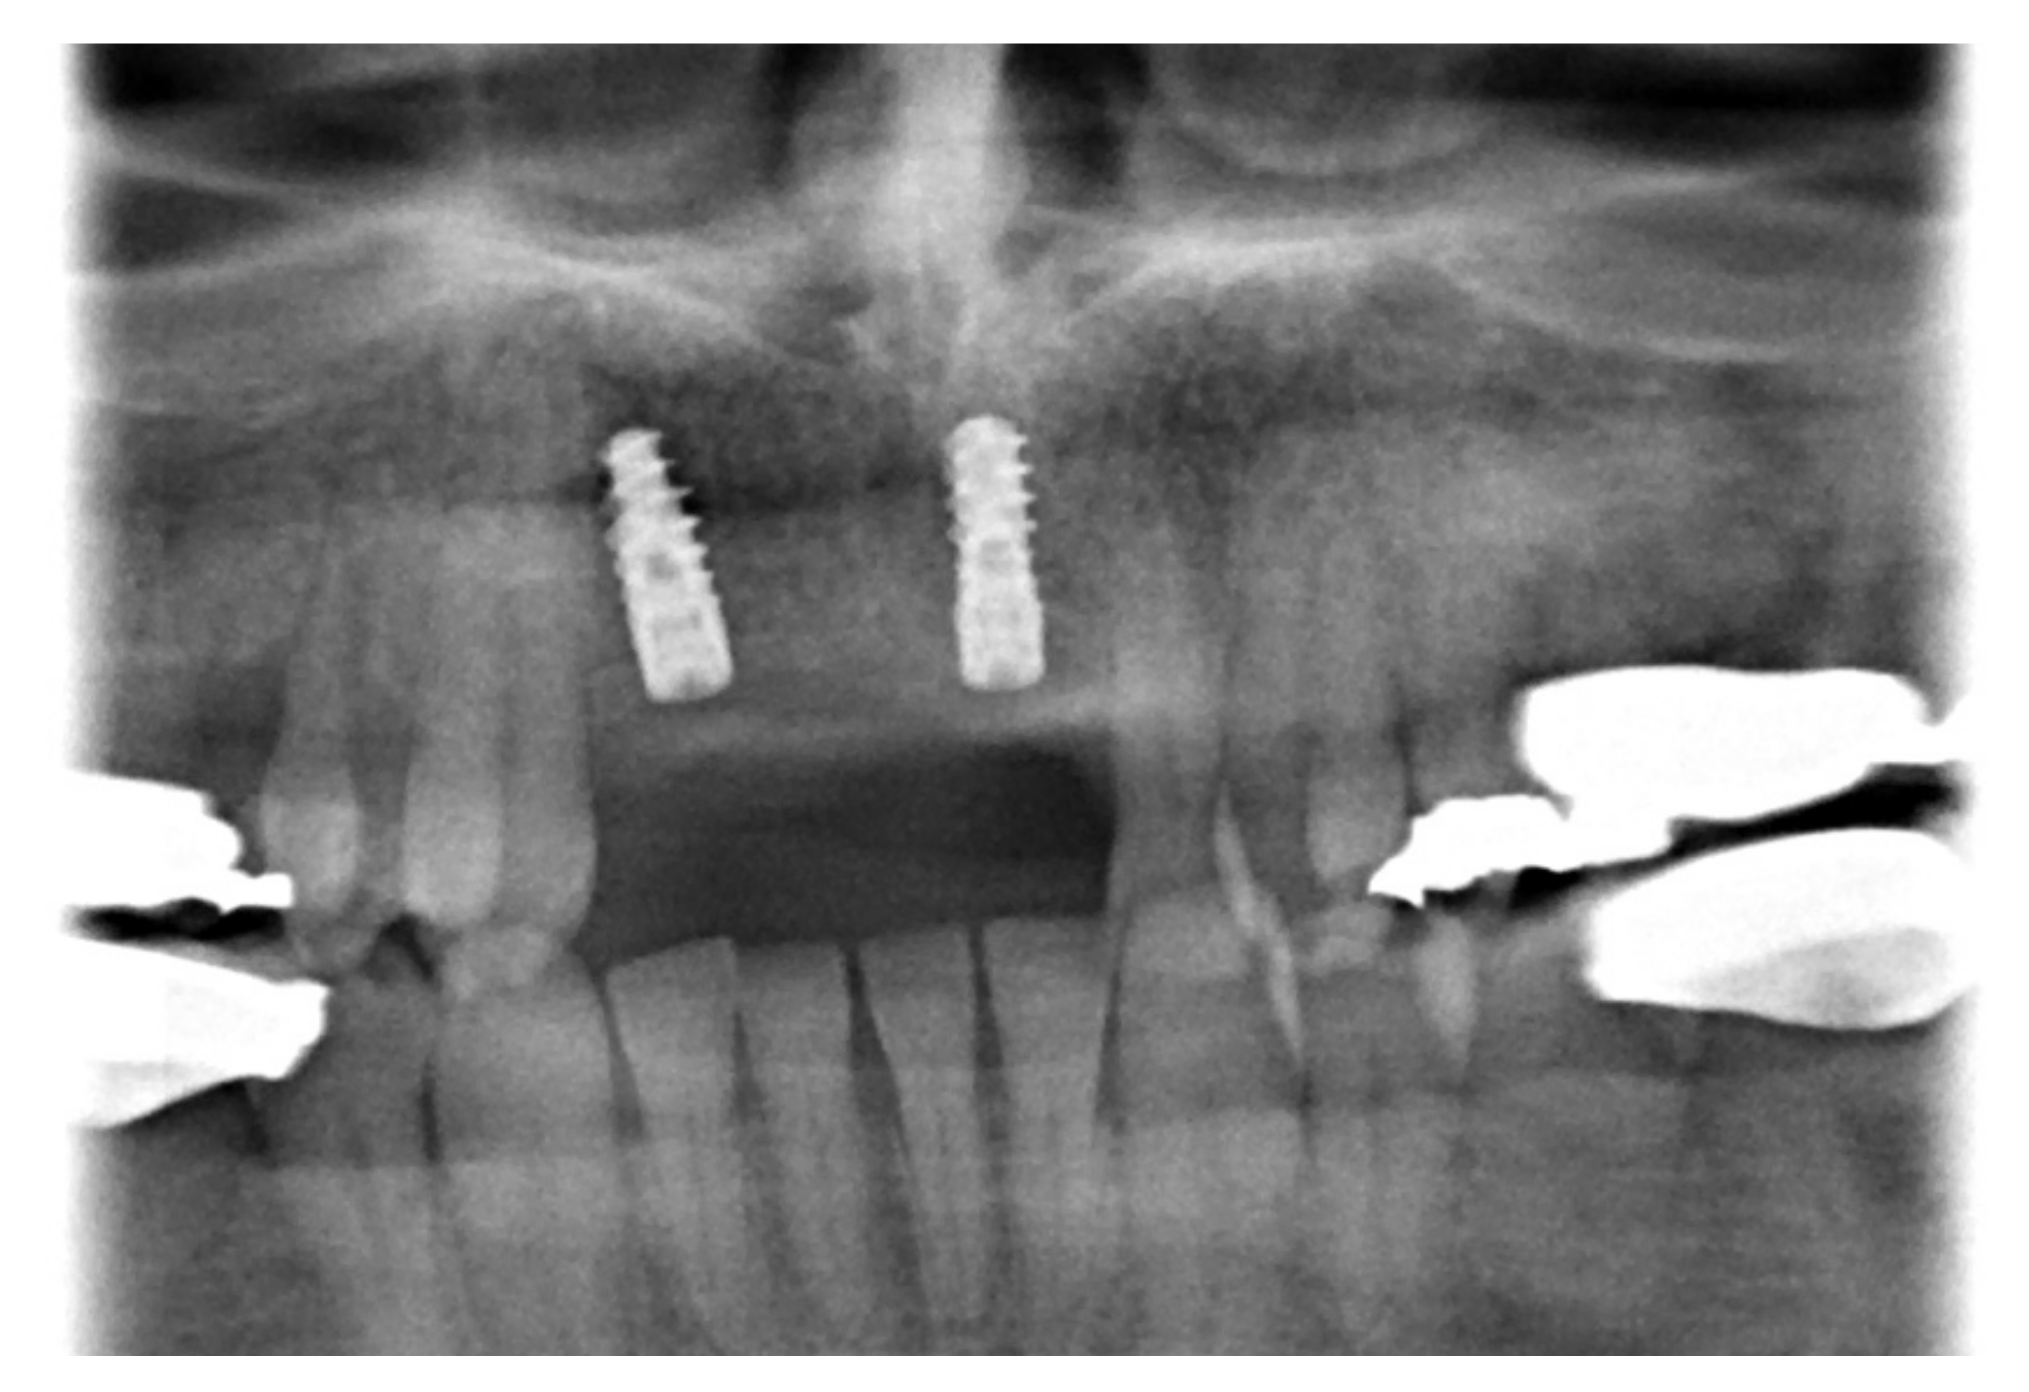

2. Case Report